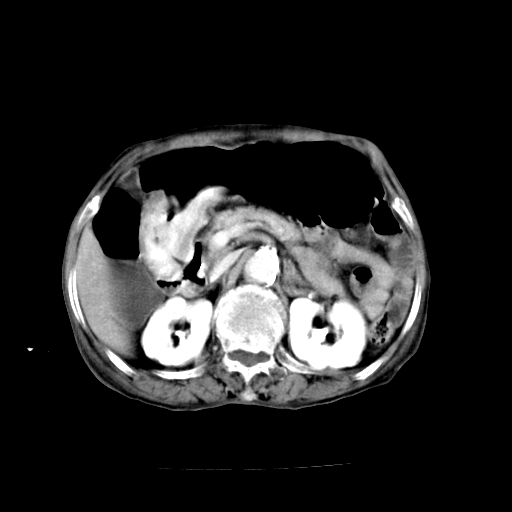

标题: CT19149:女,68岁,腹胀、恶心两周。 [打印本页]

女,68岁,腹胀、恶心两周,先做ct平扫,当时家属不同意强化,6天后家属要求增强扫描。

1)不排除胃窦癌;建议行胃镜检查。 2)局灶性脂肪肝。腹水。

考虑:胃窦ca,腹水,脂肪肝

支持考虑1、胃窦癌?建议行胃镜!; 2、局灶性脂肪肝。  3、双侧胸腔积液,胸膜增厚